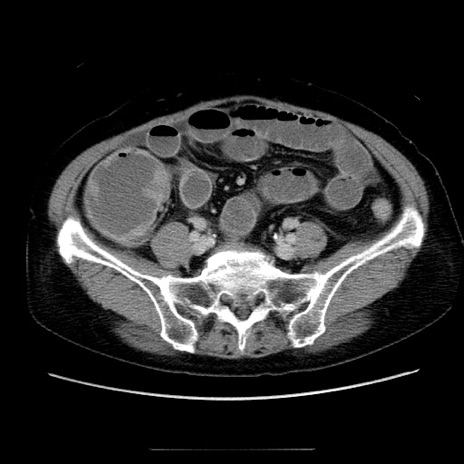

冠状断像

【症例】70歳代女性

【主訴】お腹が張る

【現病歴】1週間くらい前から腹部膨満の自覚あり。昨日夜から増悪したため、本日救急外来受診。

【身体所見】意識清明、BT 36.5℃、BP 165/106mmHg、HR 80bpm、SpO2 98%、腹部:膨満、軟、自発痛・圧痛なし、触診にて不快感あり、腸蠕動音:減弱

【データ】WBC 12600、CRP 1.04